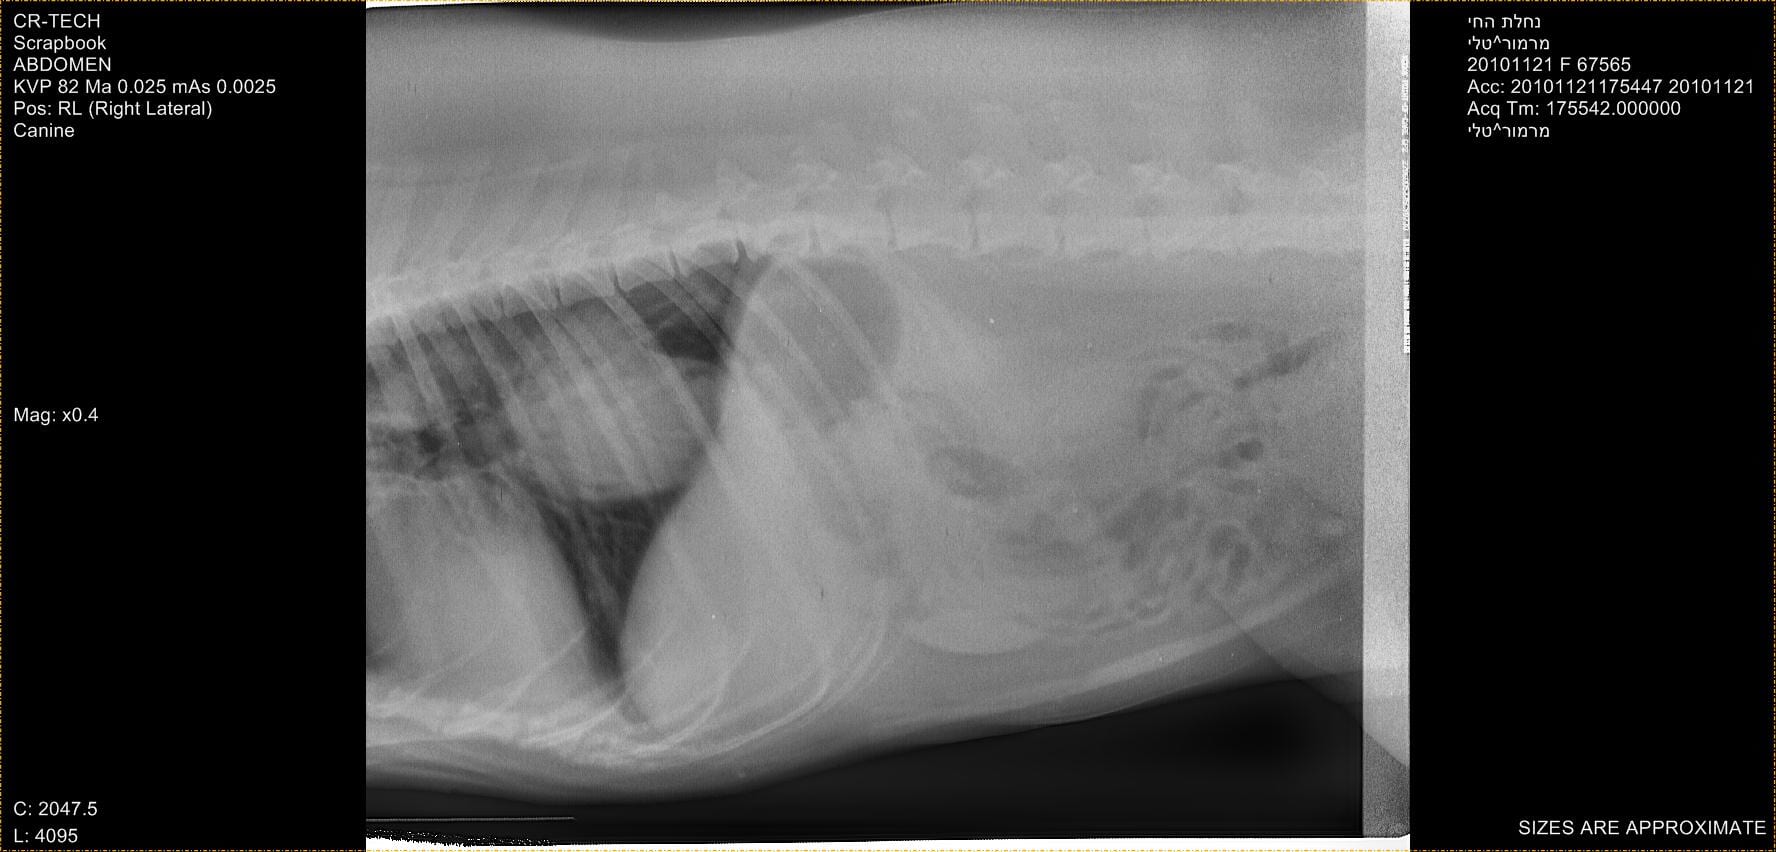

אחת הבדיקות שניתן לבצע הינה בדיקת הצפת צואה בה מנסים לאתר את ביצי התולעת תחת מיקרוסקופ. אך בדיקה זו בעייתית מאוד מכמה סיבות. ראשית, כאשר ההדבקה טריה יחסית יתכן שלא נראה ביצים בצואה מפני שהתולעת הבוגרת עדיין לא החלה בתהליך יצור הביצים. שנית, בשלבים מאוחרים של הסינדרום בהם הגרנולומה בוושט הופכת לגידול סרטני התולעת למעשה אינה קיימת עוד ברקמה ולכן לא נראה ביצים בצואה. בנוסף, מכיוון שהפרשת הביצים בצואה אינה רציפה לאורך הימים, יתכן שדגימת הצואה שלנו תיהיה נקיה מביצים למרות הדבקה.בדיקה פשוטה נוספת שניתן לבצע הינה צילום רנטגן של בית החזה. במקרים מסויימים ניתן לחשוד בגרנולומה כאשר רואים אזור בעל אטימות גבוהה יותר בוושט הטורקלית הקאודלית (בבית החזה) על רקע אונות הריאה המאווררות. אך לעיתים גרנולומות אלו קטנות ולא נראות בבירור בצילום.